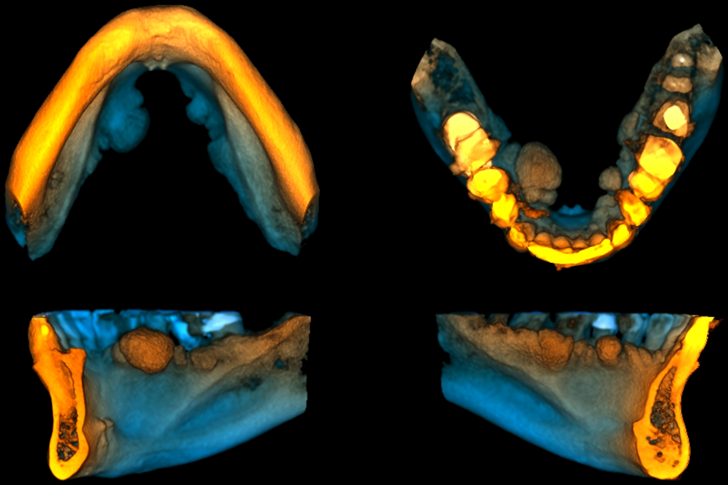

En las reconstrucciones 3D se representa Torus Lingual. (Figura 4).

RECONSTRUCCIÓN 3D